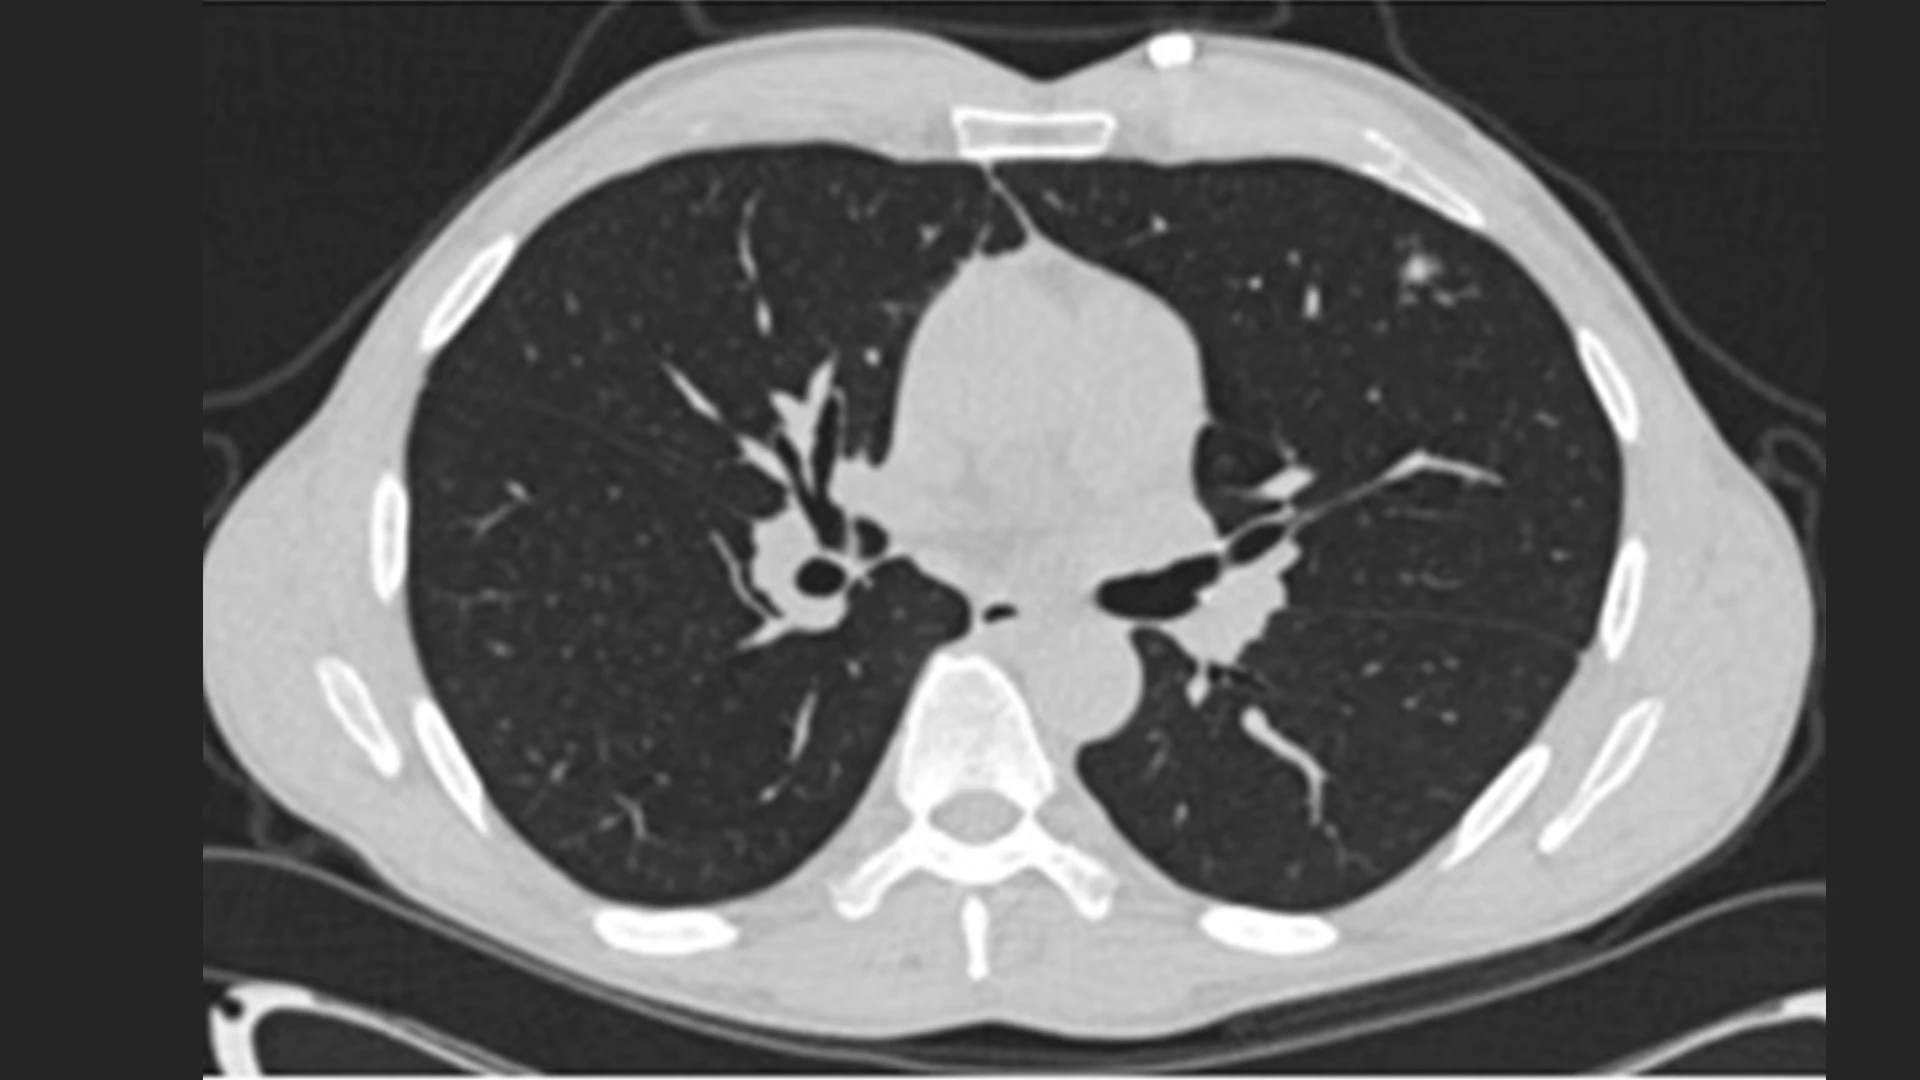

The patient's full chest CT confirmed the nodule in the left upper lobe.

The chest CT also showed a nodular infiltrate in the right upper lobe. A bronchoscopy was performed and obtained positive cultures for tuberculosis.